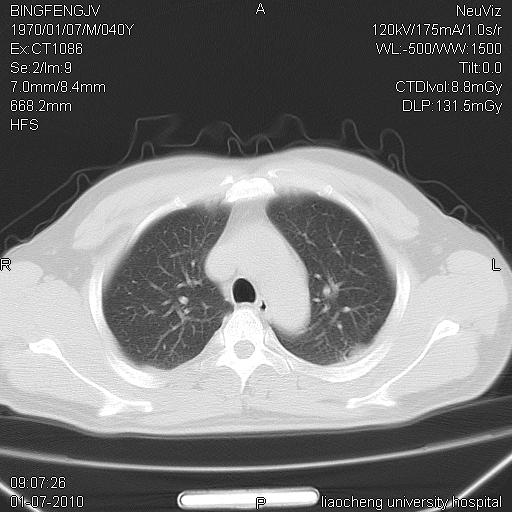

标题: CT23764B:男 40 肺部CT [打印本页]

标题: CT23764B:男 40 肺部CT

治疗2周后

炎症性病灶,继发性改变。

考虑左肺上叶近胸膜下炎症并肺气囊形成。

炎症,大部吸收。